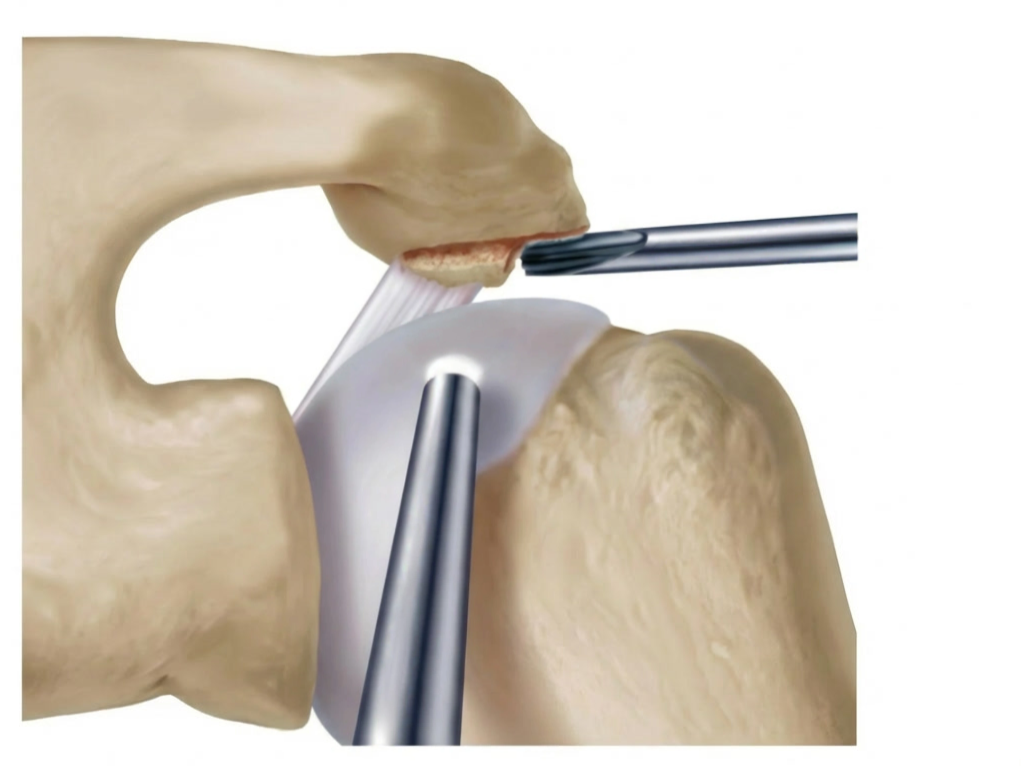

Zugang

• Einführung der Arthroskopkamera über den hinteren (posterioren) Zugang. Anlage eines weiteren vorderen (anterioren) Portales.

• Inspektion des Glenohumeralgelenks und des Subakromialraums, des Schleimbeutel und der Rotatorenmanschette

Darstellung des AC- Gelenkes

• Abtragen von Bursa und Weichteilen über dem AC-Gelenk

• Schonung der Kapsel und der coracoclaviculären Bänder (wichtig für Stabilität!)

Abtragen der lateralen Clavikula

• Abtragung von ca. 5-10 mm des lateralen Klavikulaendes

• Instrumente:  motorisierte Shaver

• Kontrolle: ausreichender Spalt ohne Knochenkontakt bei Bewegung